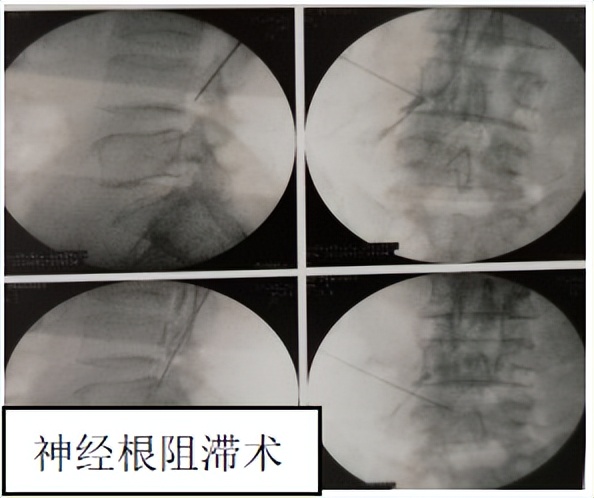

※介入治疗

○ 选择性神经根阻滞 :为目前治疗疼痛的常用诊治手段,具有精准定位、治疗的作用。

○ 椎间盘射频消融术 :是治疗盘源性腰痛的有效方法,具有目的明确、创伤小、疗效佳的特点。